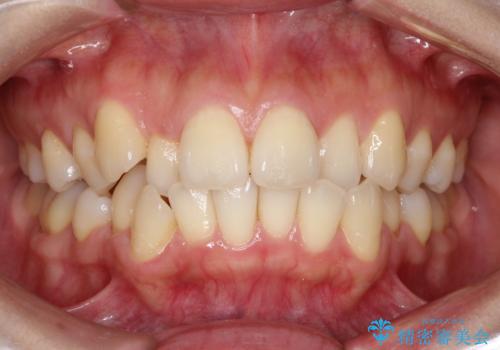

前歯が前後反対にかんでいる インビザラインによる目立たない矯正

- 前歯のかみ合わせを主訴に来院されました。

なるべく目立たずに矯正をしたいとのことで、インビザラインで矯正をすることとしました。

歯と歯の間をわずかに削り、ガタガタを改善しました。

目立たずに矯正を終えることができて、喜んでいただけました。